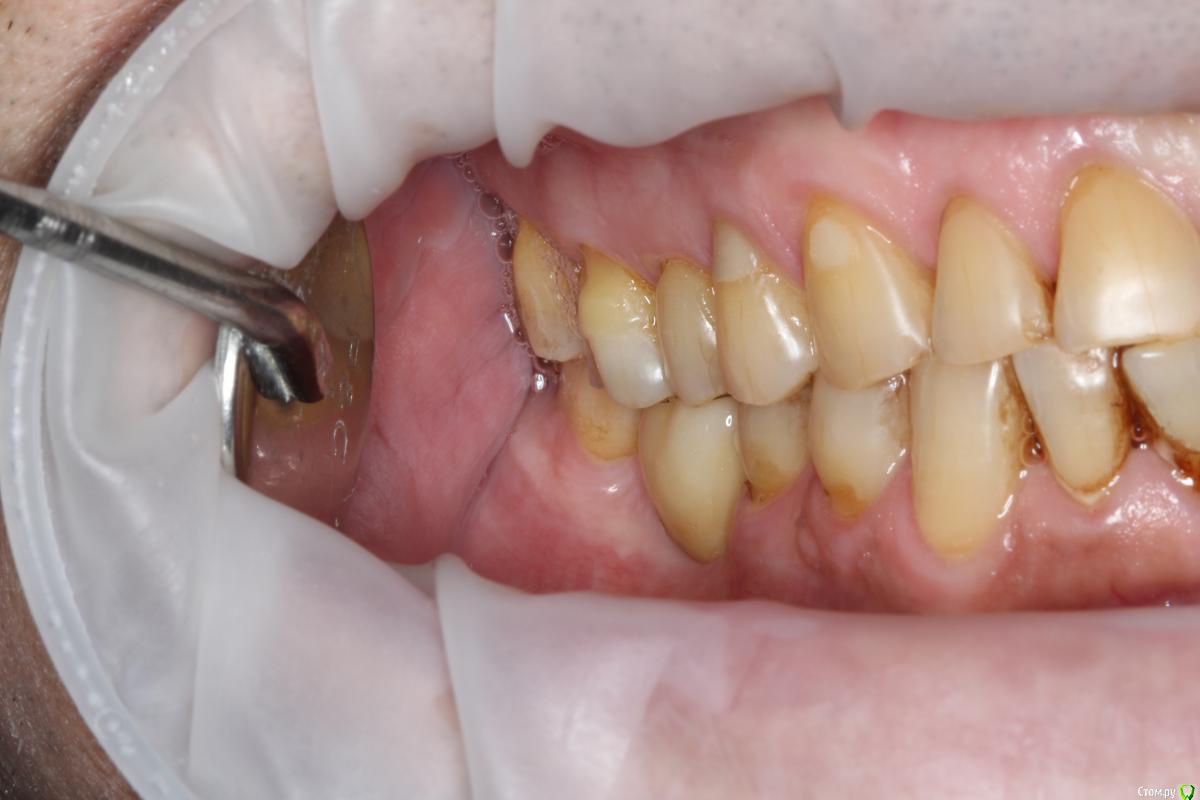

Robinbobin Опубликовано 27 марта, 2015 Поделиться Опубликовано 27 марта, 2015 (изменено) Пациент 57 лет с жалобами на стираемость зубов,чувствительность и бруксизм Хотелось бы услышать ваше мнение!!!! Изменено 27 марта, 2015 пользователем Robinbobin Ссылка на комментарий

Robinbobin Опубликовано 28 марта, 2015 Автор Поделиться Опубликовано 28 марта, 2015 а с чем к вам этот пациент пришел с какой проблемой?С жалобами на стираемость,чувствительность зубов!!! Ссылка на комментарий

Robinbobin Опубликовано 28 марта, 2015 Автор Поделиться Опубликовано 28 марта, 2015 сколы керамики тут обеспечены.. да и по эстетике, лучше уж цельнозолотые Дело в том что пациент отказывается точить зубы и мы решили сделать оклюзионные накладки из прессовонной керамики Ссылка на комментарий